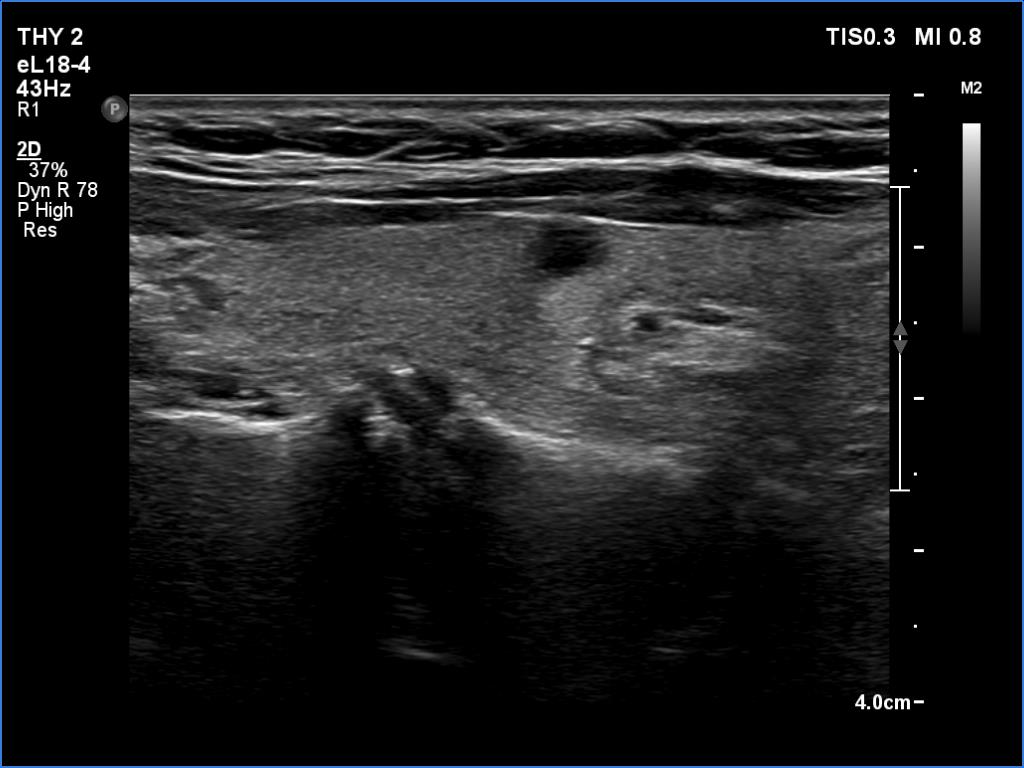

Second examination 6 month later (2nd row of images)

Clinical presentation. The patient was referred for evaluation of hyperparathyroidism. Elevated calcium and parathyroid hormone levels were found during the first evaluation. (These findings were not yet available when I first examined the patient.) Further evaluation disclosed a hyperfunctioning right lower parathyroid. The patient was operated on but no parathyroid tissue was found on histopathology. (A more experienced parathyroid surgeon was quarantined at the scheduled time of the operation, so a less experienced colleague performed the surgery.) Both hypercalcemia and hyperparathyroidism have persisted.

Palpation: no abnormality.

Laboratory tests: parathormone 129 pg/ml (normal value: 12-88), serum calcium 2,89 mM/L, phosphate 0,71 mM/L.

Ultrasonography revealed a hypoechoic mass corresponding to the right lower parathyroid.

Cytology resulted in benign lesion, a pattern which corresponded to a parathyroid adenoma.

The patient was reoperated and histopathology disclosed a parathyroid adenoma according to the right lower parathyroid.

If we compare the first and second ultrasound examination, it is evident that the ultrasound examination was not performed according to the rules of the profession at the first visit. (I will just mention that although in this case we only videotaped part of the entire study, we obviously overlooked the parathyroid gland under the right lobe. The reason for this is that we did not examine the part below the thyroid in the transverse section, and in the longitudinal section we started to examine the lower part of the thyroid too medially.)